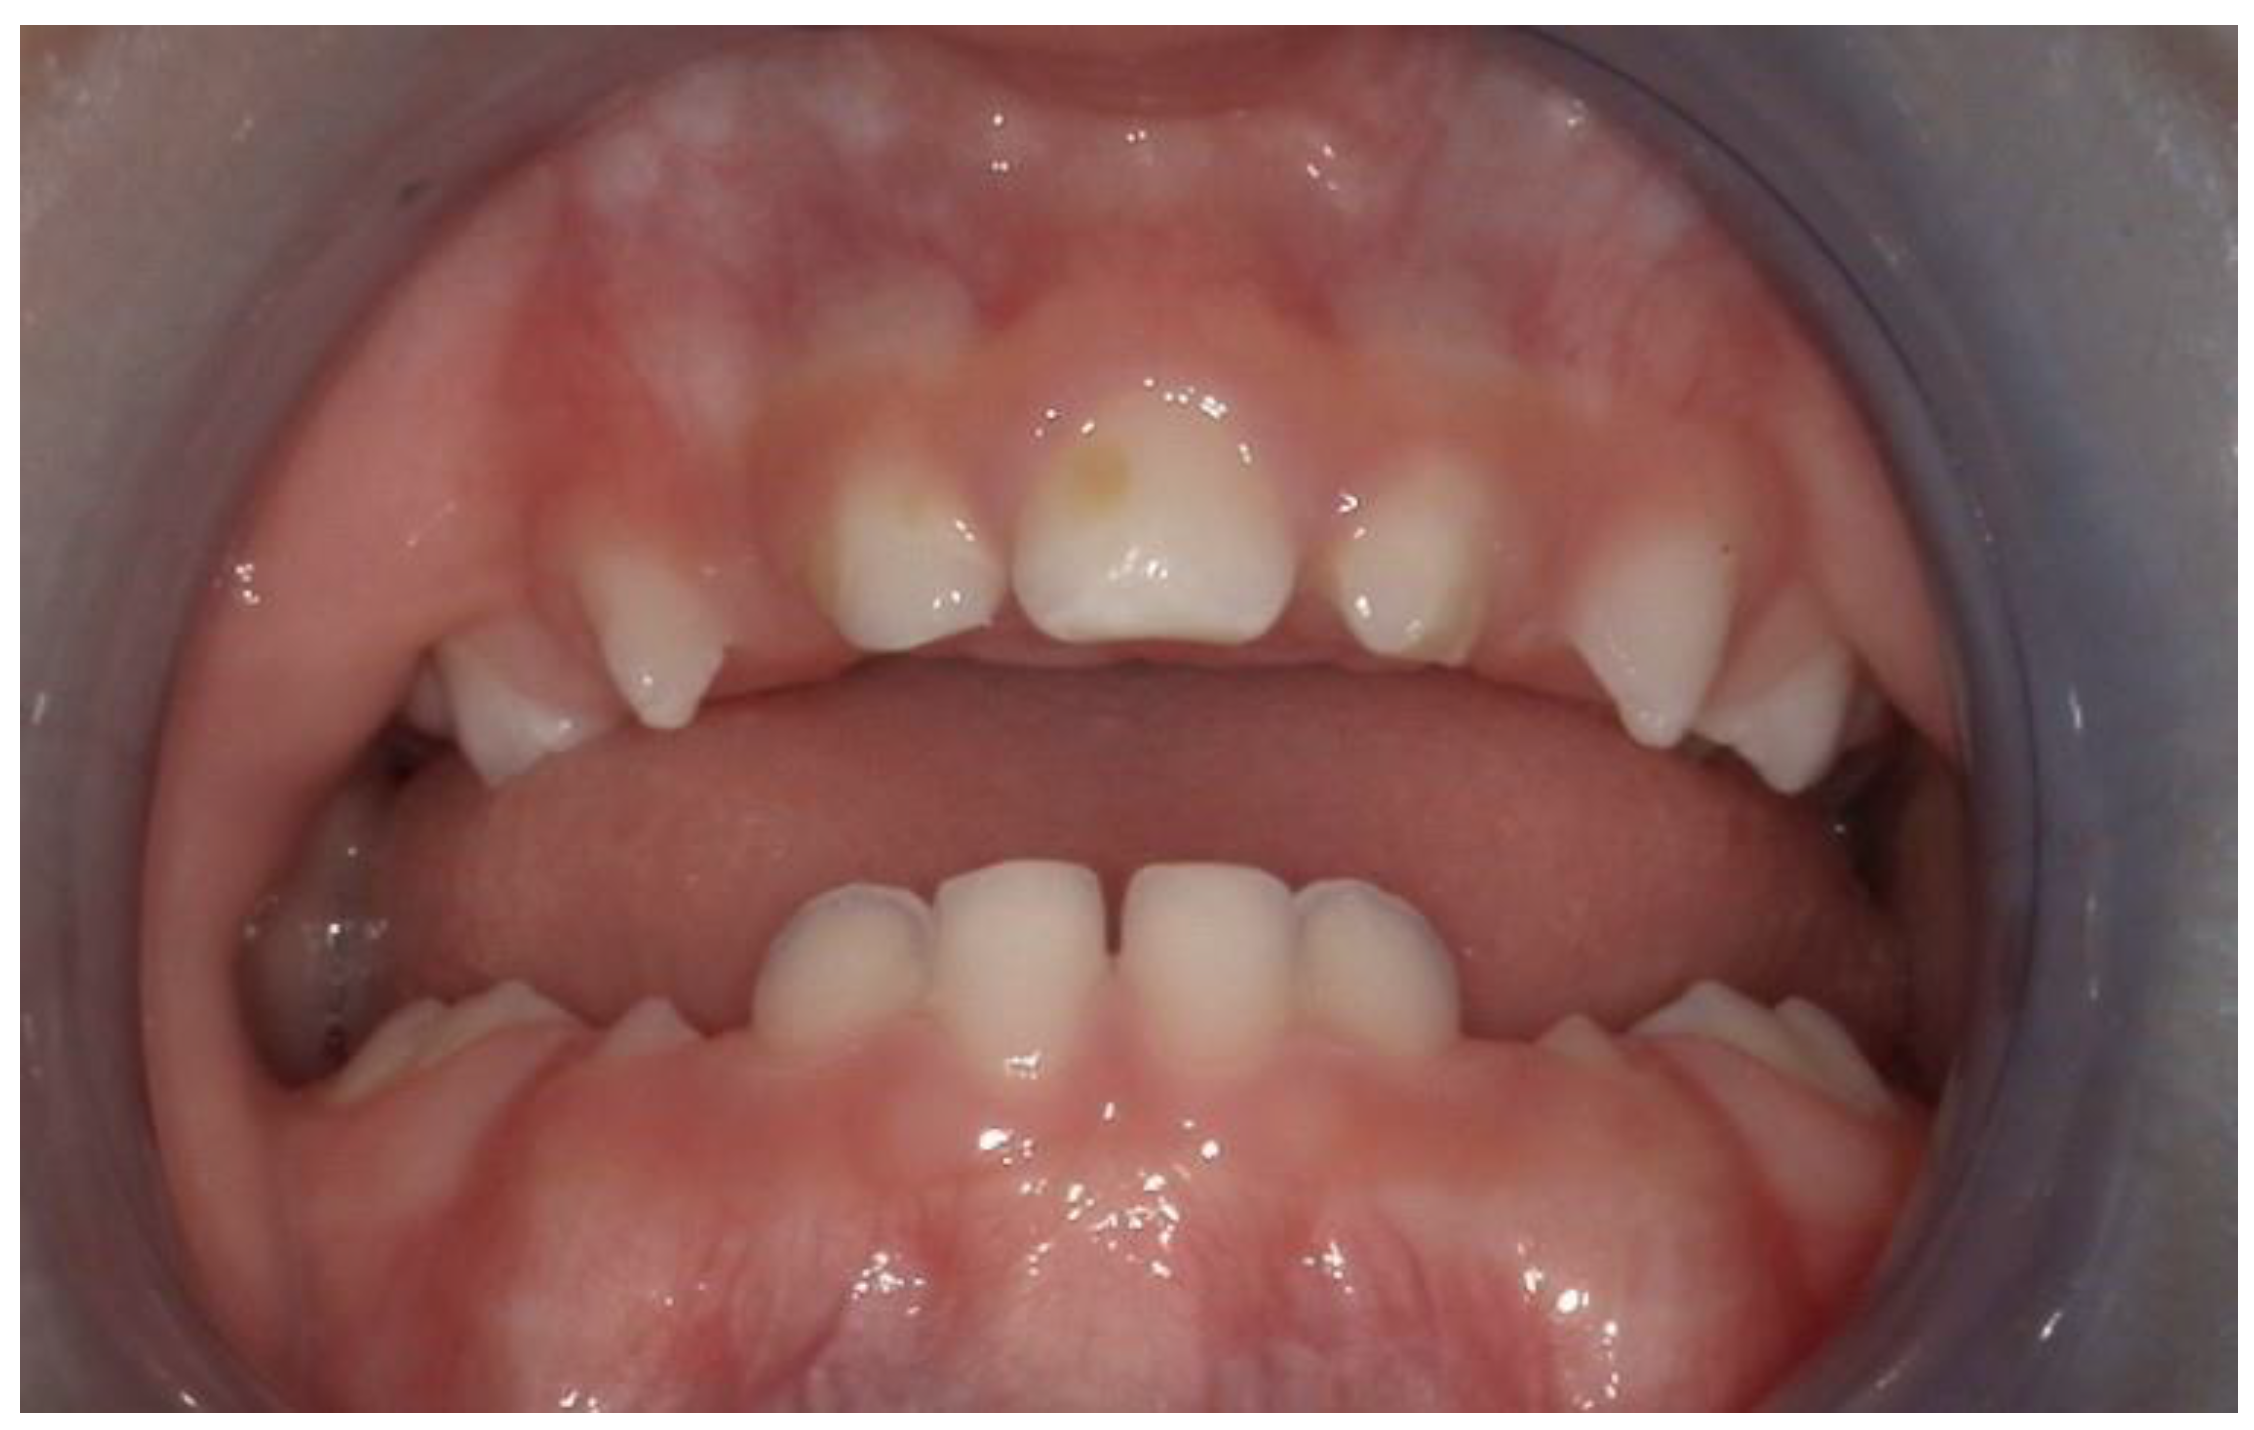

We present the rare case of an infant with HPE and CNPAS complicated by acute respiratory failure. The concomitant presence of an SMMCI was treated using a combined otorynolaringological–orthodontic approach. The multidisciplinary minimally invasive treatment involved a team comprising a neonatologist, a geneticist, a pneumologist, an ENT (ear, nose, and throat) doctor, and a pediatric dentist. The following is a detailed description of the events, the therapeutic path, and the long-term follow-up of the patient. An 8-day-old girl was admitted to the Neonatal Intensive Care Unit (TIN) of the Bambino Gesù Children’s Hospital (Rome, Italy). The baby was born at 39 weeks by caesarean section, with a birth weight of 2820 g and a length of 47.3 cm. The Apgar score was 8/10. During the clinical examination at birth, the following clinical signs were observed: cutaneous syndactyly of the II-III toes bilaterally, hypotelorism, low weight, and short stature. Respiratory distress and cyanosis ensued after a few hours. The patient was ventilated with neo-puff without much benefit. The infant was then administered CPAP (continuous positive airway pressure) and was intubated on the second day of life due to the worsening of her overall condition. Brain and facial mass MRI (magnetic resonance imaging) were performed at the birth hospital, revealing a congenital nasal pyriform aperture stenosis and the presence of a solitary median maxillary central incisor. On the eighth day of life, the patient was referred to the Bambino Gesù Children’s Research Hospital where she underwent the following tests: abdominal ultrasound, eye examination with negative results, GH, FSH, LH, cortisol, thyroid hormones, and ACTH levels, the results of which were all in the normal range. The infant also underwent an echocardiogram, which showed evidence of pervious foramen ovale. After evaluation at the Medical Genetics Department, molecular analysis showed a heterozygous variant of the GLI2 gene, for holoprosencephaly, which is classified as a class IV variant arising de novo, and which was absent in the DNA extracted from the blood of the parents. Pathogenetic variants of the GLI2 gene are associated with an autosomal dominant form of holoprosencephaly (HOLOPROSENCEPHALY 9; OMIM # 610829) with variable phenotypic expression and, in some cases, incomplete penetrance [14]. The infant was then evaluated by the ENT doctor, who performed a nasal endoscopy using a flexible laryngoscope under general anesthesia, which revealed the presence of mesenchymal bridges obstructing the right nasal cavity and a left-convex dislocation of the nasal septum. After this evaluation, the ENT doctor decided to proceed with the lysis of mesenchymal bridges, and subsequently a gentle dilation of the nasal cavities (Hegar of increasing caliber up to 4) was performed. After the widening of the nasal cavities, stabilization was achieved through balloon dilation, and two trans-nasal stents with small calibers (2.5 in one nasal cavity and 3 in the other) were placed. The infant was simultaneously evaluated by a pediatric dentist who specialized in orthodontics. The dentist found evidence of the following clinical signs: the palate had a markedly ogival shape, with growth in the direction of the anterior vertex; the median raphe palatine was severely depressed; and there was a reduction in the transverse diameters of the upper jaw. In the operating room, the dental team took an impression of the palate with addition silicone in order to create an intraoral device (Figure 1). After the surgery, given the presence of the characteristic palatal deformity, a decision was made to increase the respiratory space by applying a device. On the same day, a neonatal palatal expander plate (NPEP) [13] was built by a dental technician and positioned in the upper arch (Figure 2). The device was a mucous anchoring plate made of acrylic resin, which was extended buccally with flanges to ensure good retention [13]. A screw was placed at the center of device, to correspond with the palate median suture. To avoid any risk of suffocation, the team inserted a safety wire through two holes in the canine region. The safety wire was a surgical silk suture thread (without a needle) of approximately 70 cm in length. The orthopedic maxillary expansion therapy was initiated in order to favor the distraction of the palate at the level of the median palatine suture and assist the nasal dilation. A precise protocol for the use of the orthodontic device was established, and the child responded very well. The saturation and frequency remained regular during the insertion maneuvers, and the child kept the device in her mouth throughout the procedure. We recommend activating the central screw of the device 24 h after insertion (Figure 3). In this case, for the first day, the infant wore the device for two hours, three times a day. On the subsequent days, the device was worn for three hours, three times a day, under the constant supervision of the parents or caregivers. Immediately after the insertion of the device, the patient started swallowing and sucking normally, demonstrating that the physiological sucking–swallowing mechanism had been activated. Five days after surgery, the stents were removed and the girl was able to breath on her own, with a few episodes of desaturation that spontaneously resolved. Subsequently, the clinical condition of the child remained stable, and the follow-up visits with the ENT specialists and the orthodontist showed positive results: she resumed spontaneous breathing with good saturation (97%), her bottle feeding was going well and she had gained weight, and a valid nasal respiratory space had been secured, which was associated with the rosy appearance of the soft tissues of the oral cavity. After 15 days, the use of the expansion device was suspended and the patient was discharged. The patient underwent follow-up visits once a month for the first six months and thereafter every six months for the monitoring of respiratory function and airway patency, dental eruption, the stability and health of the median maxillary central incisor, and the growth of the jaw complex (Figure 4).

Figure 2. The patient at the time of the first application of the neonatal palatal expander plate (NPEP).